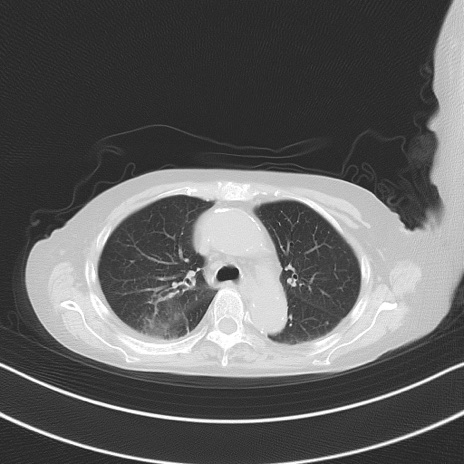

横断像

他院CT